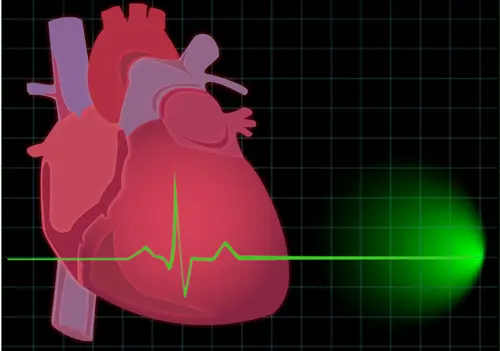

Em contraste a paragem cardíaca é causada por uma arritmia cardíaca súbita chamada fibrilação ventricular. Na fibrilação os sinais elétricos dentro do coração de repente se tornaram caóticos. Porque esses sinais elétricos controlar o tempo e a organização dos batimentos cardíacos, quando os símbolos degeneram para o caos total, o coração de repente pode parar. Ou seja, gera a “parada cardíaca”. O resultado comum é a morte súbita! O tratamento para a parada cardíaca é começar a ressuscitação cardiopulmonar imediata (CPR) para apoiar a circulação da vítima. Logo que possível é necessário entregar um grande choque elétrico ao coração com um dispositivo chamado “desfibrilador”. O grande choque permite que o sinal elétrico do coração se reorganizar para o órgão começar a bater de novo. Não se pode ignorar que a morte ocorre em poucos minutos de parada cardíaca, a menos que a ajuda de especialistas esteja disponível. Grande maioria dos indivíduos não é ressuscitada com sucesso. Parada cardíaca tende a ser comum em pessoas que têm vários tipos de doença cardíaca subjacente, um ataque cardíaco prévio ou qualquer condição que produz insuficiência cardíaca. De fato, pacientes que tiveram ataque cardíaco ou insuficiência cardíaca devem ser considerados para a inserção de um desfibrilador cardíaco implantável, aparelho que ressuscita automaticamente as pessoas que sofrem paradas cardíacas. Outras causas de paragem cardíaca incluem certas anomalias hereditárias que tendem a aumentar o risco de fibrilação ventricular e o uso de várias drogas (em especial cocaína). Se um parente próximo morreu é importante tentar saber a causa exata da morte. Seu risco de ataque cardíaco e de alguns tipos de parada cardíaca pode ser maior se um parente próximo experimentou os eventos. Certifique-se de obter o máximo de informações que puder.